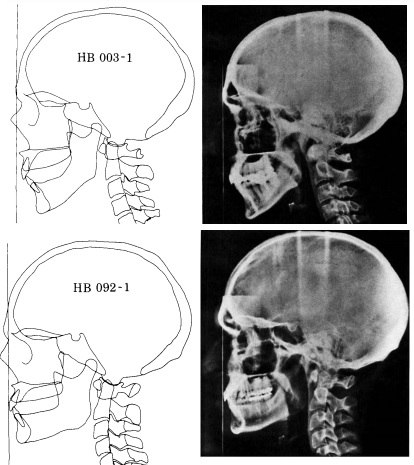

Here's evidence that craniofacial development can affect your posture.

musclesfhp.jpg

fhprx.jpg

protactionextension.jpg

According to this theory If the neck muscles are in continuous tension it can propagate to the galea and compress it's tissue. Then an anti-inflammatory response is activated and male pattern baldness starts.

I might really have it's weight since we observed that men with very poor craniofacial features must have very good galea in order not to bald. And that sometimes If you have relatively small galea but very poor cranofacial features it can't save you and you start balding.